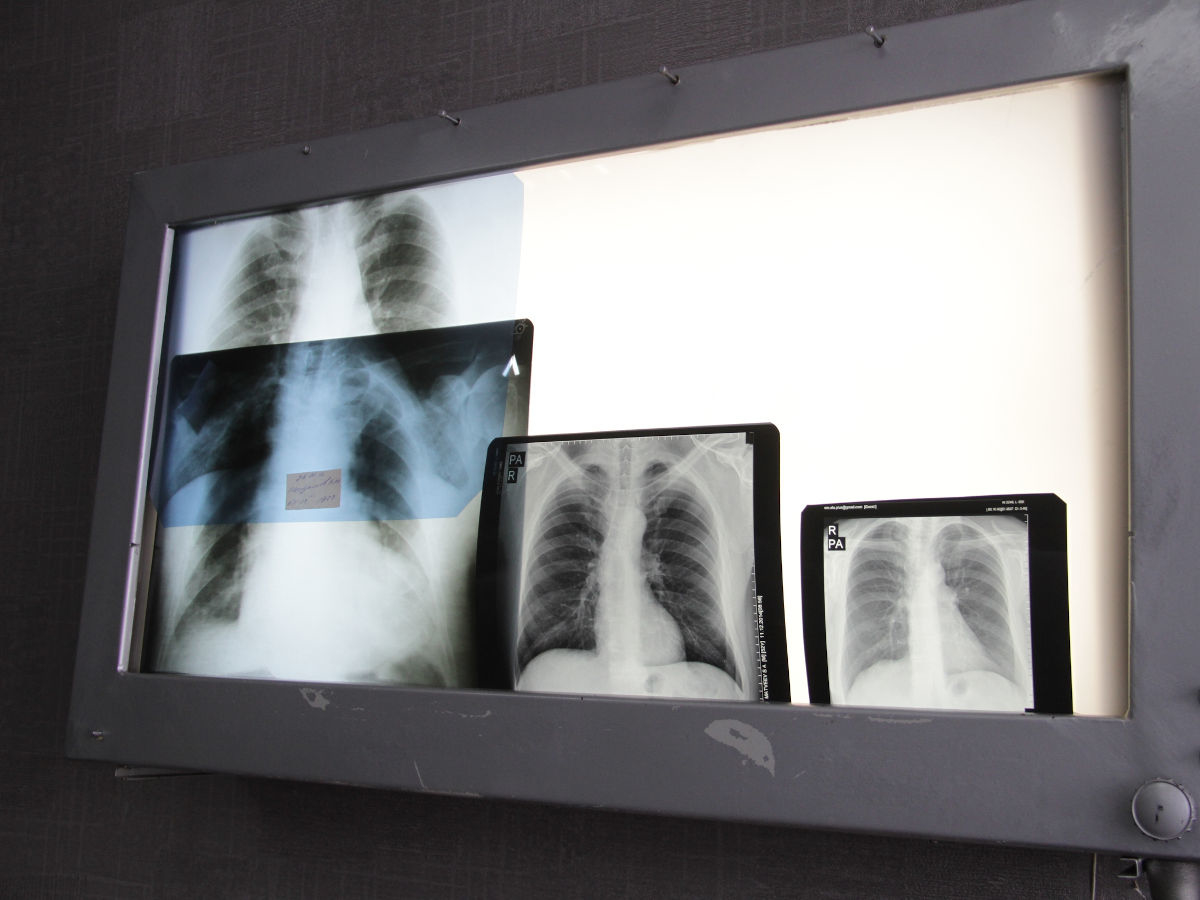

«Халық арасындағы аурулардың алдын алу және салауатты өмір салтын насихаттау мақсатында осы жылдың тоғыз айында 9 мыңнан астам шара ұйымдастырып, 70 мыңға жуық адам қамтылды. B гепатитімен сырқаттану 100 мың халыққа шаққанда 0,14 құрап, аурушаңдық деңгейі 66,6%-ға төмендеді. Туберкулезге шалдыққандар көрсеткіші 10,1%-ға азайды», — деді ол.